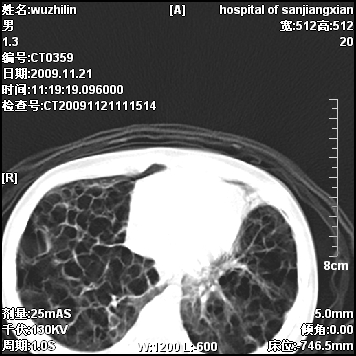

弥漫性薄壁囊腔,胸膜下及肺底部占优势,双上肺磨玻璃密度影,首先考虑特发性肺间质纤维化,其次囊性肺纤维化,肺淋巴管平滑肌瘤病嗜酸性肉芽肿等;要结合临床综合考虑。

两肺布满多个薄壁含气囊腔,以下肺居多,伴磨玻璃样密度影,左侧气胸。两肺发育不全、两肺多发肺囊肿并感染,其次考虑肺囊腺瘤。